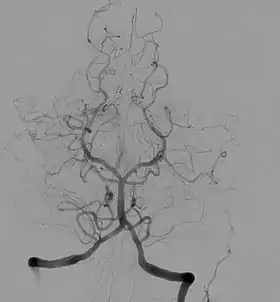

Cerebral Angiography

Introduced in 1927, cerebral angiography enabled doctors to accurately detect and diagnose anomalies in the brain such as tumors and internal carotid artery occlusions. Over the course of a year, Egas Moniz, the inventor of cerebral angiography, ran experiments with various dye solution percentages that were injected into arteries to help better visualize the blood vessels in the brain before discovering that a solution consisting of 25% sodium iodide was the safest for patients, as well as the most effective in the visualization of blood vessels and arteries within the brain.[7]